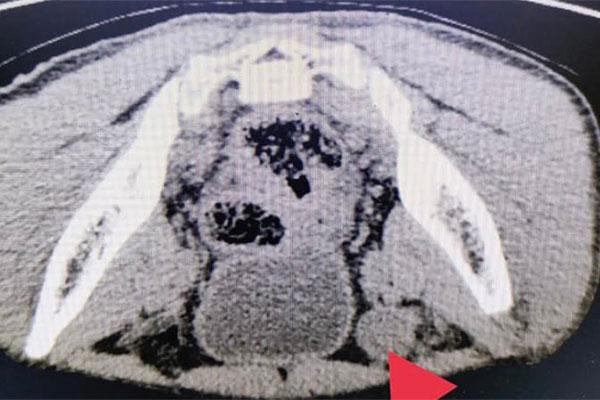

Kết quả xét nghiệm và chẩn đoán hình ảnh cho thấy: tinh hoàn bên phải không có trong bìu, mà nằm sâu trong ống bẹn, kích thước nhỏ hơn bình thường 36x15mm.

Sau khi xác định được vị trí tinh hoàn ẩn trong ổ bụng. Qua hội chẩn chuyên khoa, các bác sĩ chẩn đoán bệnh nhân bị tinh hoàn lạc chỗ và chỉ định phẫu thuật hạ tinh hoàn ẩn cho bệnh nhân.